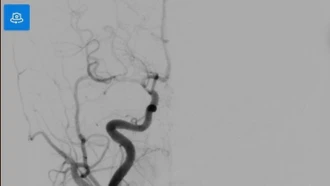

Gần đây, Bệnh viện Trung ương Quân đội 108 tiếp nhận nhiều ca đột quỵ ở trẻ nhỏ và vị thành niên, trong đó có bệnh nhi chỉ 8 tuổi. Căn bệnh vốn được coi là của người lớn nhưng lại xuất hiện ngày càng nhiều ở người trẻ tuổi.